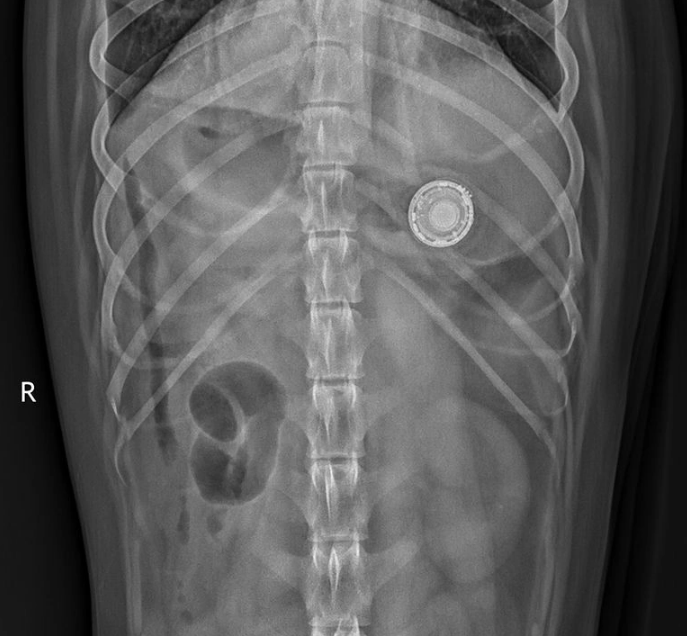

据《华尔街日报》报道,宠物主人科林・莫蒂默(Colin Mortimer)发现狗圈上的AirTag找不到了。当使用“Find My”来让AirTag播放声音时,发现养的另一条狗的肚子里传来了声音,无法吐出就只能通过手术取出。这样的事件不止一例,在很多社交平台上都有网友在吐槽。

AirTag的大小与硬币相当,采用圆形盘状设计,戴在宠物项圈上非常方便。但是对于中型、大型宠物来说,还是很容易发生误吞食的情况,家中养宠物的朋友还是要稍微注意一下。